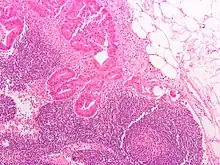

Local cancer in many parts of the body can cause lymph nodes to enlarge because of tumorous cells that have metastasised into the node.[35] Lymph node involvement is often a key part in the diagnosis and treatment of cancer, acting as "sentinels" of local disease, incorporated into TNM staging and other cancer staging systems. As part of the investigations or workup for cancer, lymph nodes may be imaged or even surgically removed. If removed, the lymph node will be stained and examined under a microscope by a pathologist to determine if there is evidence of cells that appear cancerous (i.e. have metastasized into the node). The staging of the cancer, and therefore the treatment approach and prognosis, is predicated on the presence of node metastases.